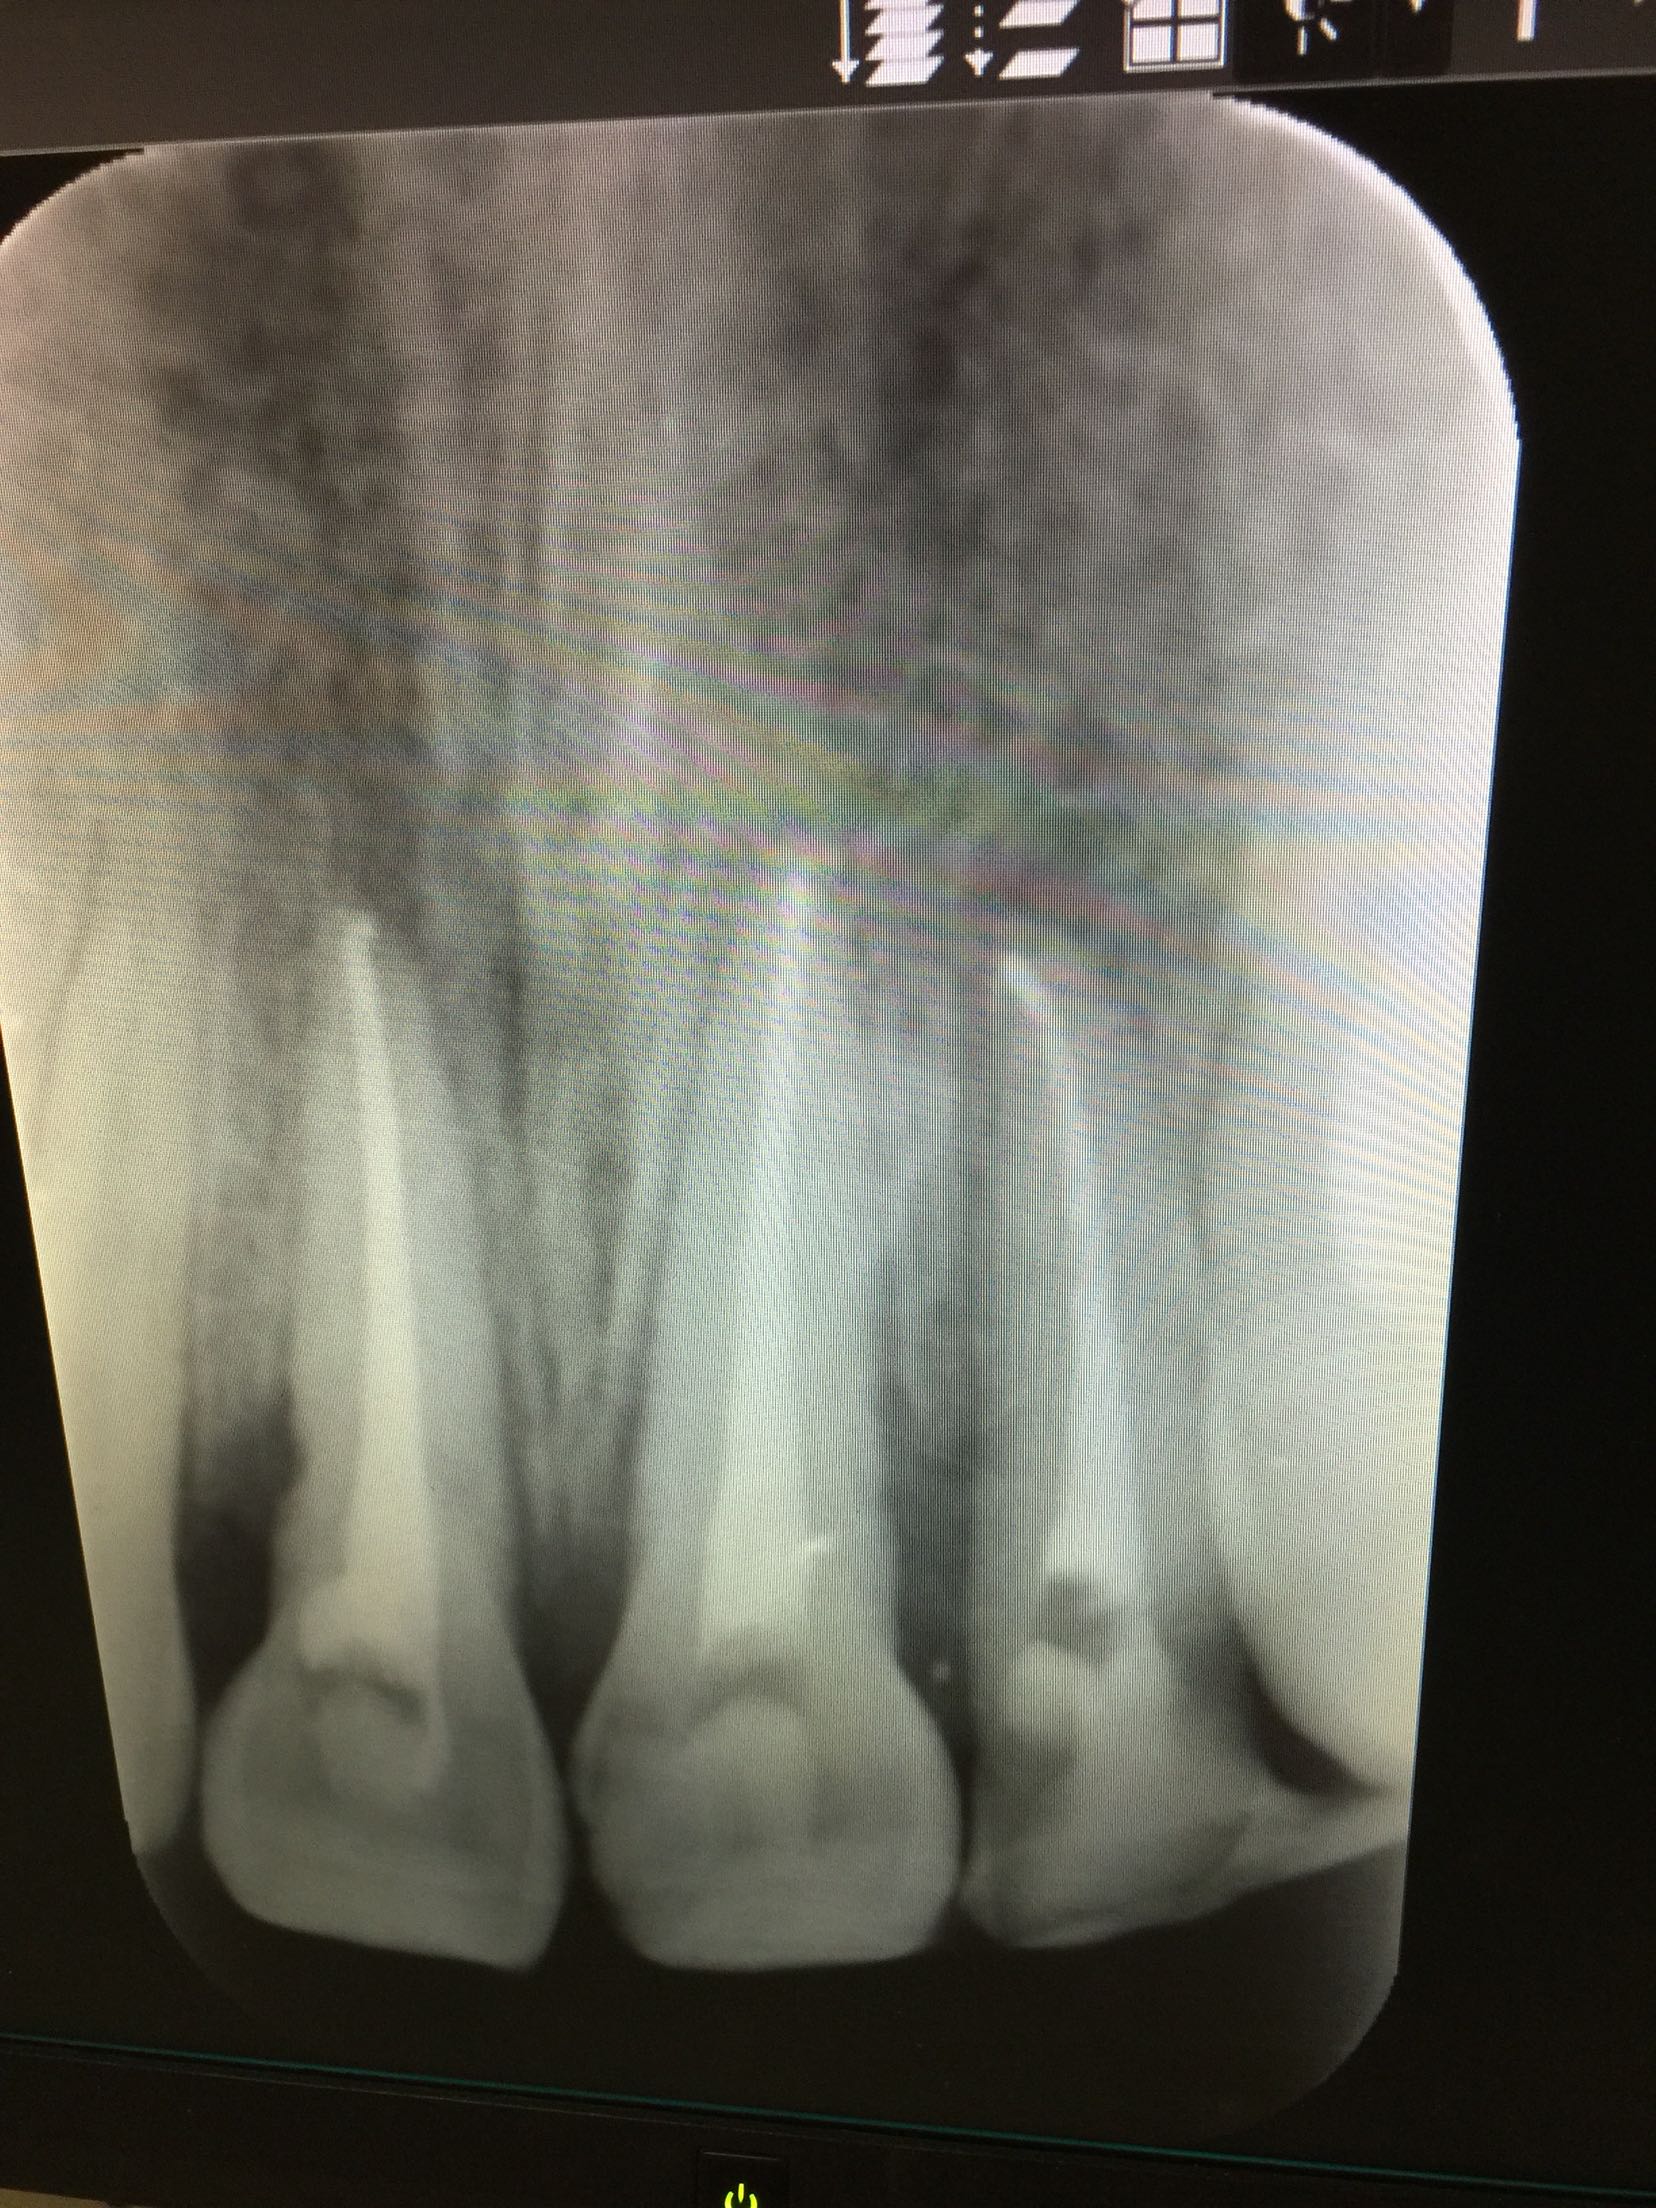

诊断:11牙21牙侧向移位 22牙复杂冠根折 上颌骨骨折 治疗计划:11,21牙请颌外会诊 22牙拔除折裂片后试情况制定下一步治疗计划。 请颌外会诊上颌骨骨折 治疗:患者于外科行上颌骨骨折固定求及拔除22牙折裂片后行13-23松牙固定术后。来我科行11.21.22牙根管治疗术。开髓后清扩,消毒,封veta-pex。两周后复诊。 复诊,诊间无不适。试主尖

根充

择期冠修复。